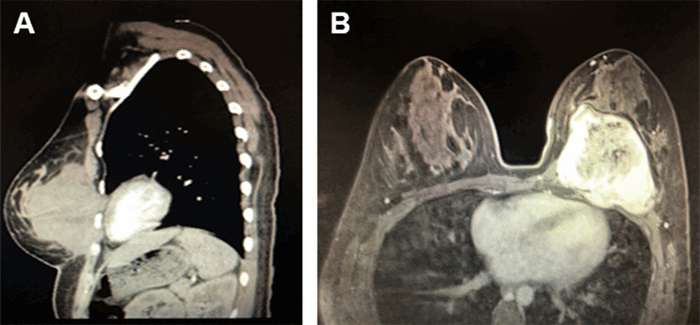

Further imaging work up at that time included magnetic resonance imaging (MRI) identifying a 10 cm × 7 cm × 9 cm solid mass arising from or adjacent to the medial chest wall, posterior to the breast parenchyma, with invasion through the pectoralis major and insinuation into the chest wall intercostal muscles between the third through sixth ribs at the costochondral junction. The mass displaced the normal fibroglandular and fatty breast tissues anteriorly (Figure 1). Comprehensive genetic counseling and testing were done and were negative for pathogenic mutation.

Figure 1. Solid Mass Arising from or Adjacent to the Medial Chest Wall. Published with Permission.

A) Sagittal CT scan showing 10 cm × 7 cm × 9 cm mass in left breast invading chest wall; B) Transverse MRI scan showing 10 cm × 7 cm × 9 cm mass in left breast invading chest wall